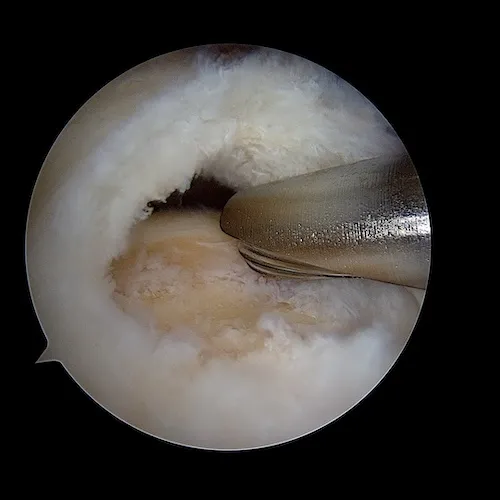

La surface osseuse est ensuite préparée. L'os est avivé grâce à une fraise motorisée. Ce geste permet la revascularisation du tendon réinséré et la cicatrisation sur l'os.

On utilise ensuite un pointeau qui permet de forer un orifice dans l'humérus . C'est dans cet orifice que va être placée l'ancre miniaturisée sur laquelle sont fixés les fils.

L'ancre sur laquelle sont fixées les sutures est vissée. Nous utilisons des ancres en PEEK et des ancres résorbables. Nous évitons dans la mesure du possible d'utiliser des ancres métalliques.

Le tendon est ensuite réparée après passage des sutures au travers du tendon. Une deuxième rangée d'ancres permet de plaquer le tendon contre l'os.